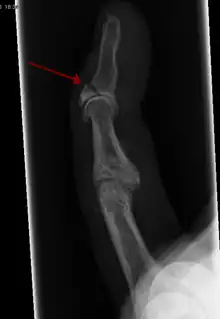

![]() |

Oblique fracture | Diagonal to a bone's long axis (more than 30°) | ||